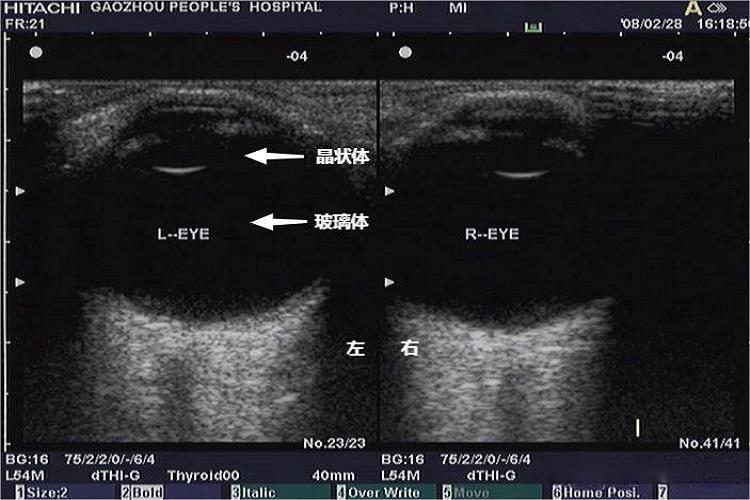

眼部的眼球呈球形,最前面的是角膜,呈高回声带,角膜与晶状体之间为前房,内为房水。晶状体形如碟形,边缘为高回声,中心为无回声,固定于晶状体囊内。玻璃体为透明无回声区。周围是眼球壁,普通超声不能分辨视网膜、脉络膜、巩膜。眼球壁后方“似声影”处为视乳头。另外,彩色多普勒血流显像可显示视网膜中央动脉、睫状后动脉、眼动脉及相应静脉的血流信号。

正常眼部超声可显示眼球、角膜、晶状体、玻璃体等结构,如果怀疑眼内或球后占位病变,眼部超声检查能提供有用的诊断信息。